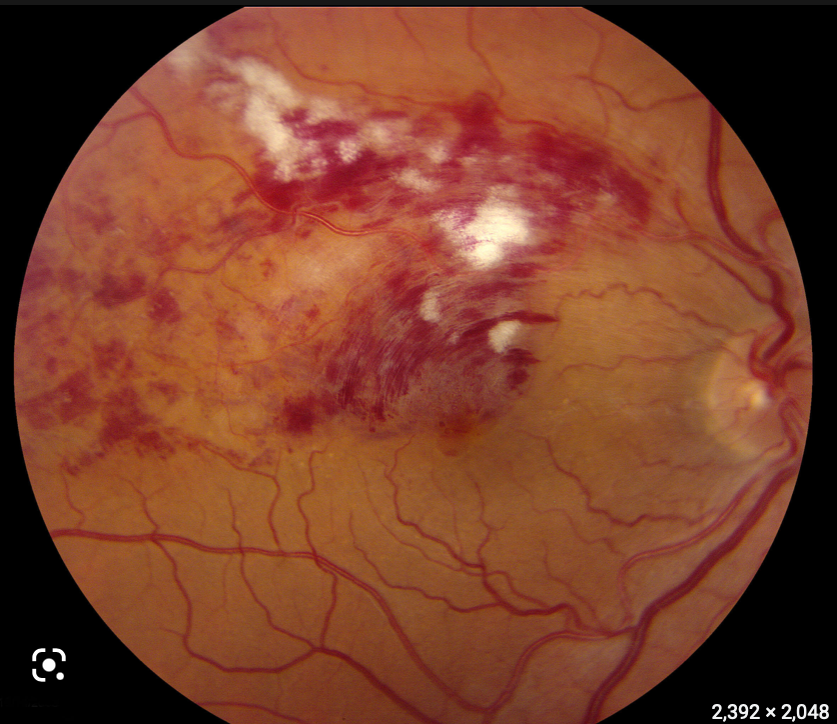

What are the signs of BRVO?

• Dilated and tortuous veins peripheral to the occlusion site

• Round/blot/flame haemorrhages

• Regional retinal oedema

• Macula oedema?

• CWS?